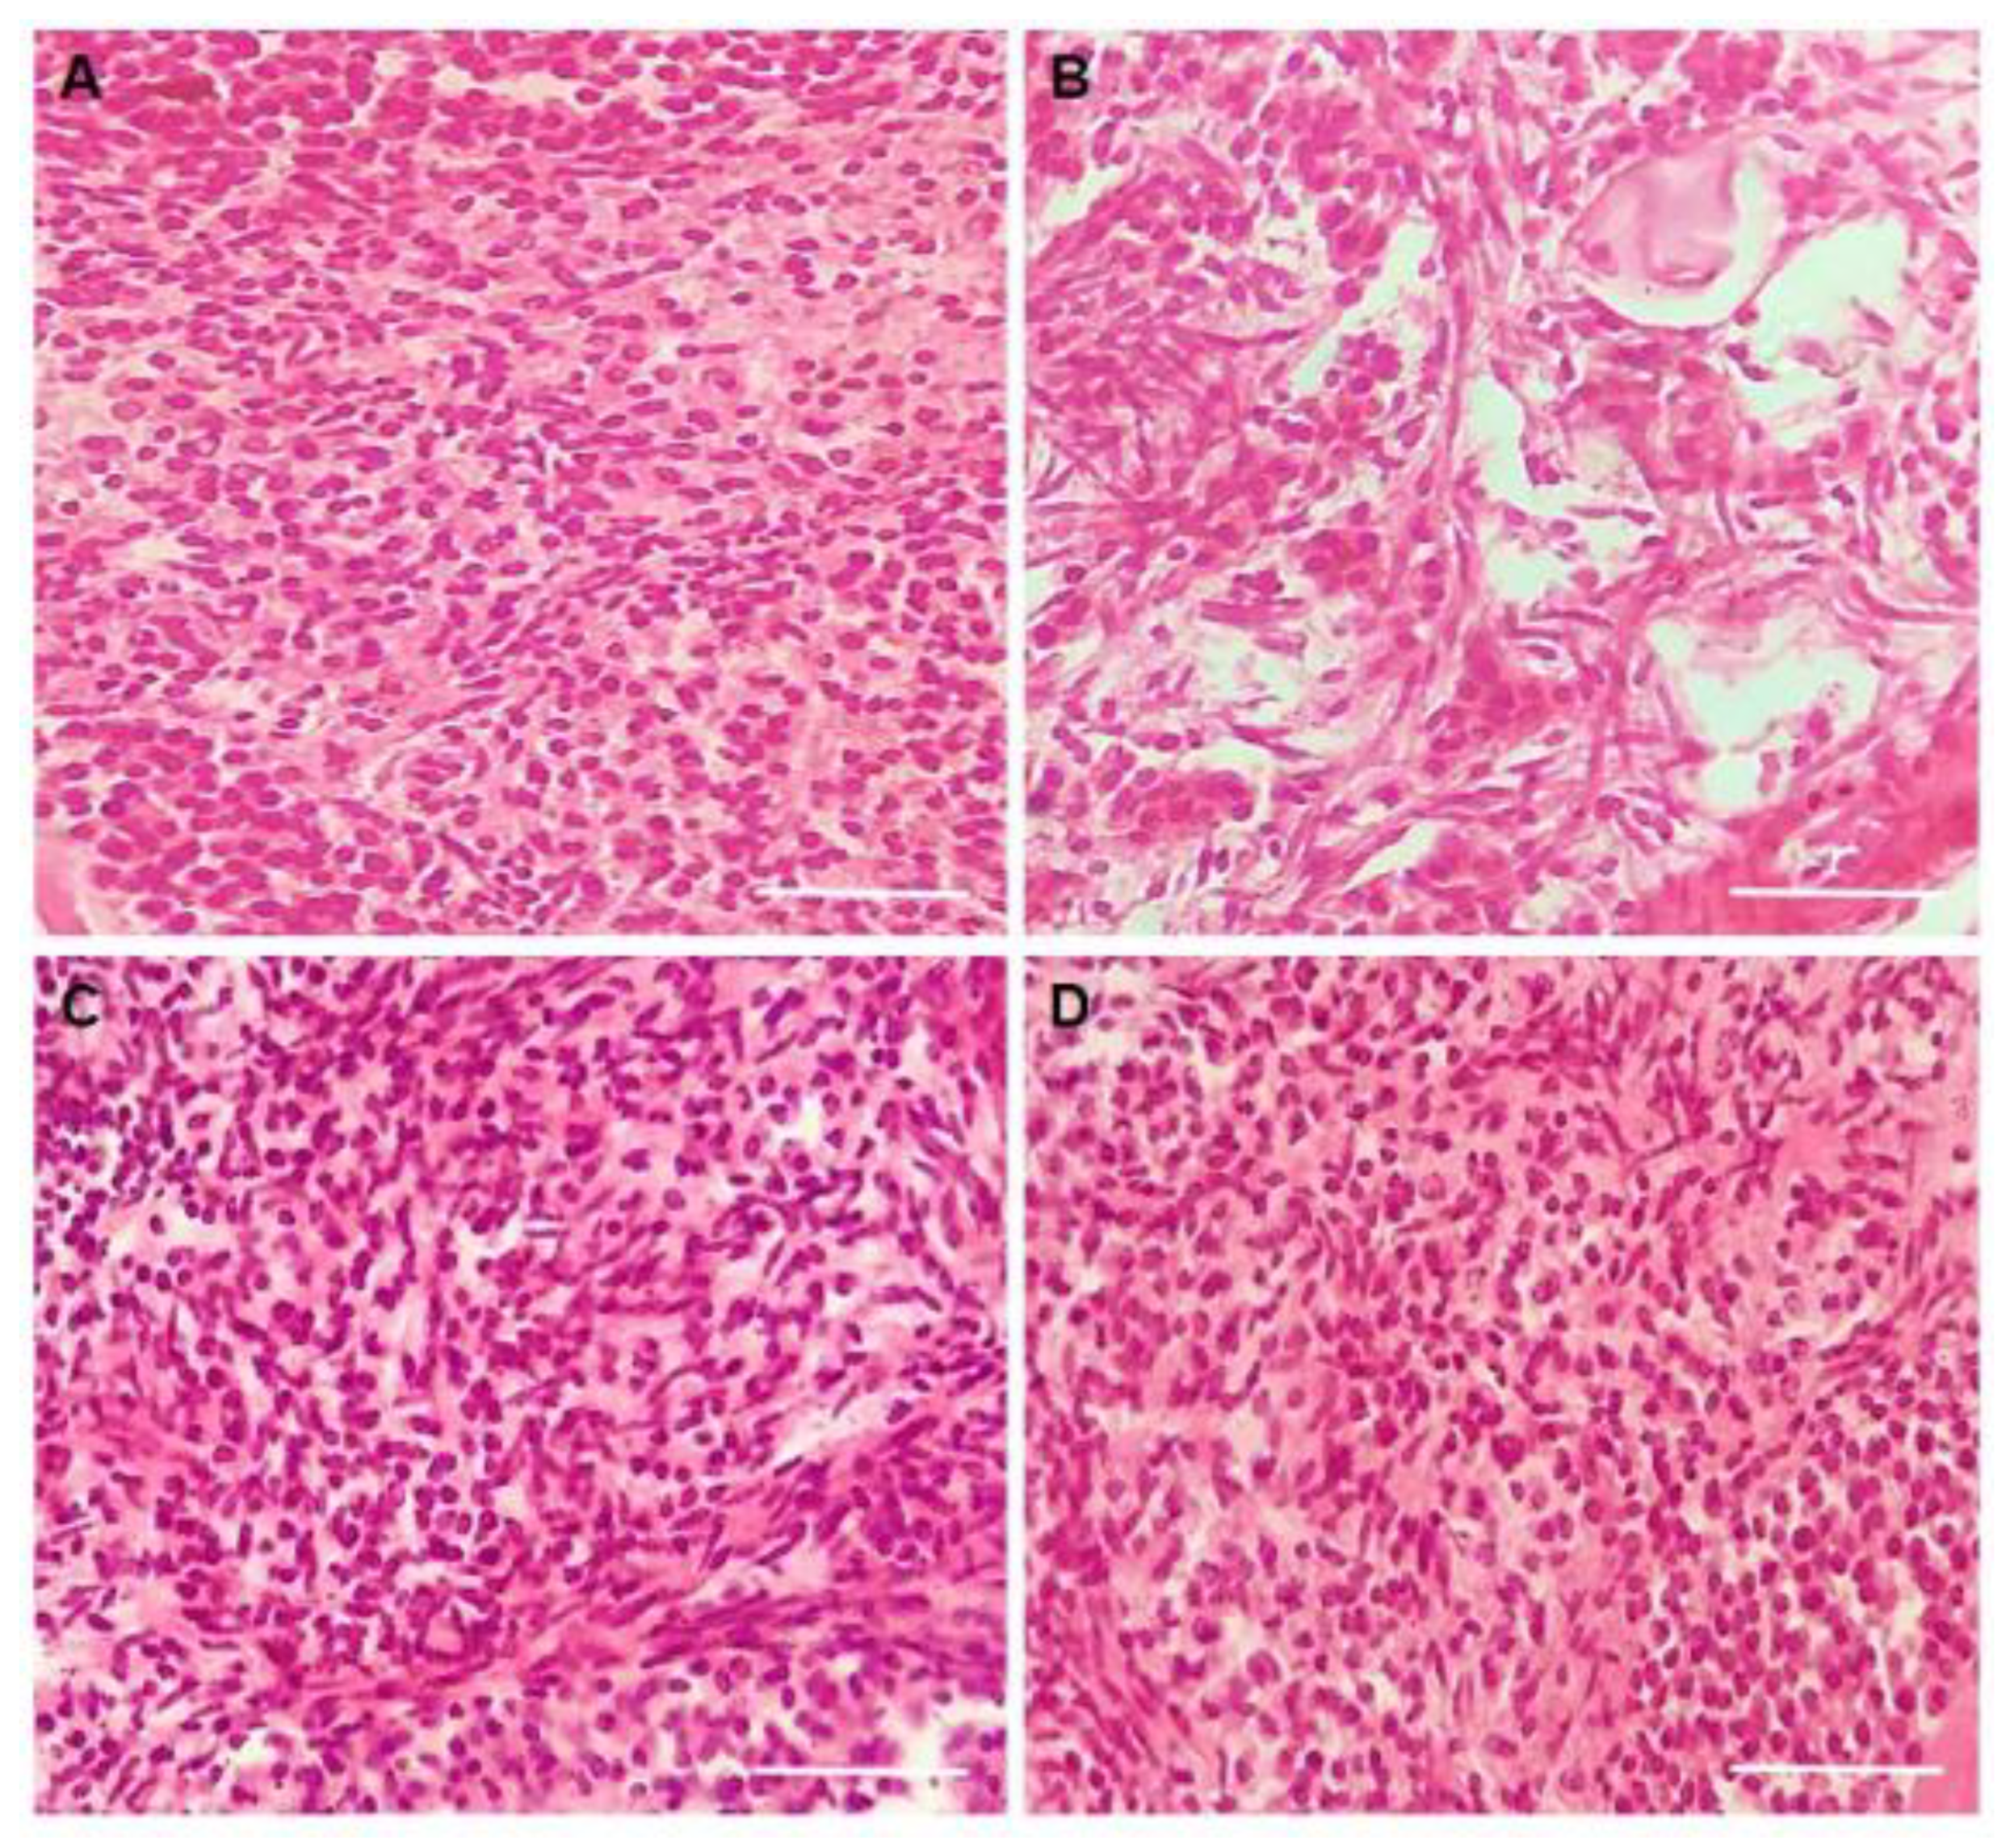

3.1. Experiment 1: Effect of CIMI on Follicular Morphology, Activation and Development after In Vitro Culture

3.3. Experiment 2: Potential of CIMI to Reduce Damage Caused by DOXO on In Vitro Culture of Mouse Ovaries

3.6. Evaluation of Stromal Cells Density after In Vitro Culture of Mice Ovaries